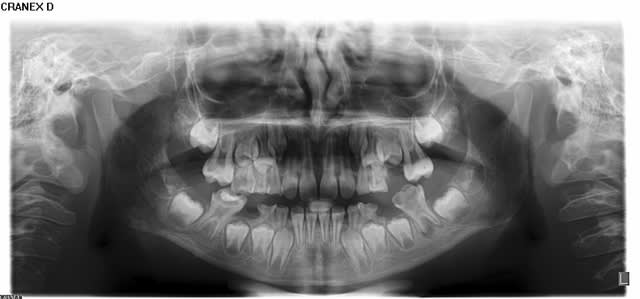

Au niveau dentaire, on observe un taurodontisme (voir molaires sur panoramique).

Il faut regarder les 6 du haut, surtout la 26. En bas, les dents sont nécrosées, le développement s'est arrêté.

L'enfant a 9 ans : compare les molaires du haut avec les pano d'enfants du même age ci-dessous.